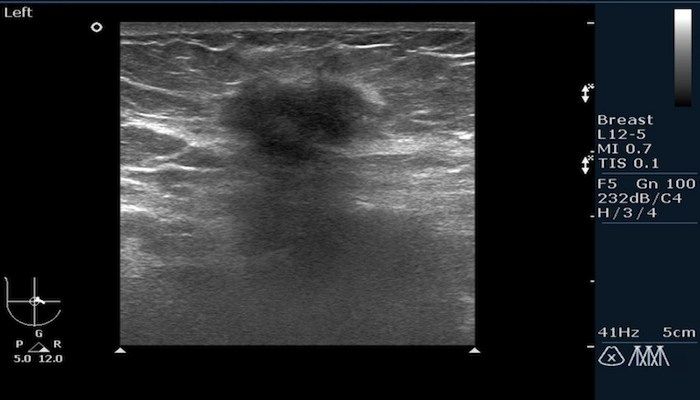

- УЗИ грудной железы — позволяет выявить гипоэхогенный участок округлой формы.

Ультразвуковое исследование поможет точно установить размеры гнойника и его расположение.